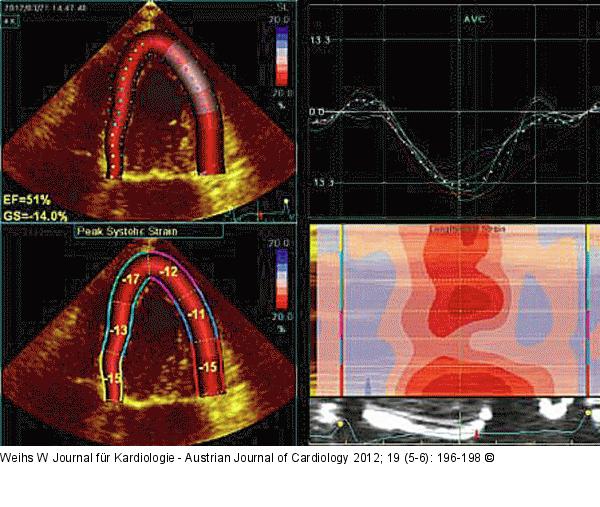

Abbildung 9: Speckletracking Speckletracking des linken Ventrikels: Geringfügig reduzierter longitudinaler Strain (normalerweise > 16 %). |

Speckletracking des linken Ventrikels: Geringfügig reduzierter longitudinaler Strain (normalerweise > 16 %). |